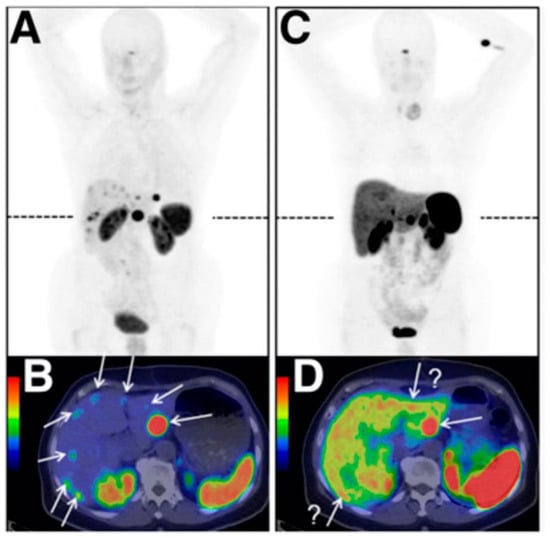

- Wild, D.; Fani, M.; Behe, M.; Brink, I.; Rivier, J.E.; Reubi, J.C.; Maecke, H.R.; Weber, W.A. First clinical evidence that imaging with somatostatin receptor antagonists is feasible. J. Nucl. Med. 2011, 52, 1412–1417. [Google Scholar] [CrossRef] [PubMed]

- Nicolas, G.P.; Schreiter, N.; Kaul, F.; Uiters, J.; Bouterfa, H.; Kaufmann, J.; Erlanger, T.E.; Cathomas, R.; Christ, E.; Fani, M.; et al. Sensitivity Comparison of 68Ga-OPS202 and 68Ga-DOTATOC PET/CT in Patients with Gastroenteropancreatic Neuroendocrine Tumors: A Prospective Phase II Imaging Study. J. Nucl. Med. 2018, 59, 915–921. [Google Scholar] [CrossRef] [PubMed]

- Fani, M.; Del Pozzo, L.; Abiraj, K.; Mansi, R.; Tamma, M.L.; Cescato, R.; Waser, B.; Weber, W.A.; Reubi, J.C.; Maecke, H.R. PET of somatostatin receptor-positive tumors using 64Cu- and 68Ga-somatostatin antagonists: The chelate makes the difference. J. Nucl. Med. 2011, 52, 1110–1118. [Google Scholar] [CrossRef] [PubMed]